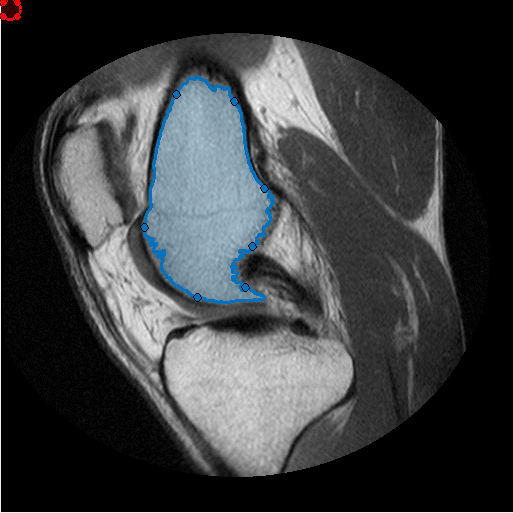

Создайте Круговой ROI, который будет использоваться в качестве средства стирания или инструмента редактирования ROI кисти. (Можно использовать любой из классов images.roi.* путем создания небольшого изменения, упомянутого ниже).

he = images.roi.Circle(... 'Center', [50 50],... 'Radius', 10,... 'Parent', gca,... 'Color','r');

Сопоставьте два прослушивателя события с Круговым ROI. Каждый слушает для перемещения ROI, и другой слушает для того, когда перемещение останавливается. ROI, перемещающий функцию обратного вызова, пример убеждается, что имел свою привязку положения к пиксельным местоположениям и также изменил цвет (Красный/Зеленый), чтобы указать, удалит ли операция редактирования или добавит к целевому ROI от руки. Если ROI редактора прекращает перемещаться, мы создадим соответствующие бинарные маски для ROI редактора и целевого ROI от руки и сделаем необходимое редактирование. Наконец, мы преобразуем обновленную маску назад к объекту ROI от руки. Обеспечьте электричеством прослушиватель, чтобы реагировать каждый раз, когда этот ROI редактора перемещен

Эта анимация показывает добавление, и удалите операцию редактирования.

Это - ROI, перемещающий функцию обратного вызова. Эта функция гарантирует, что привязки ROI редактора к пиксельной сетке, и изменяют цвет ROI редактора, чтобы указать, добавит ли это к ROI от руки или удалять область от ROI от руки. Если центр ROI редактора вне целевого ROI от руки, удаляет операцию, в противном случае это 'добавит'.